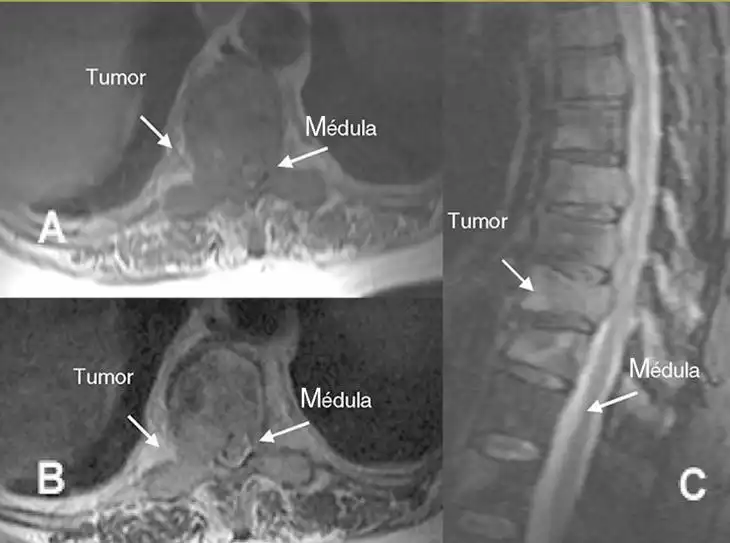

La detección temprana de cáncer es crucial, especialmente en el caso de los tumores vertebrales. Estos tumores, aunque menos comunes que otros tipos de cáncer, pueden tener un impacto significativo en la salud y calidad de vida de los pacientes. La mayoría de los tumores vertebrales son metástasis, es decir, se originan en otras partes del cuerpo y se diseminan a la columna vertebral. Las fuentes más comunes de metástasis vertebrales son el cáncer de próstata, mama, pulmón y riñón. Según un estudio reciente de la Sociedad Española de Columna Vertebral (GEER), entre el 70 y el 80% de los tumores malignos pueden provocar metástasis óseas, y de estas, aproximadamente el 70% se localizan en la columna vertebral.

Los tumores de columna vertebral se dividen en dos categorías principales: los tumores primarios y los secundarios. Los tumores primarios son relativamente raros, representando menos del 5% de todos los tumores óseos. Por otro lado, los tumores secundarios, que son metástasis, son mucho más comunes. Los tumores benignos, como el hemangioma y el osteoma osteoide, suelen localizarse en el arco posterior de la columna. En contraste, los tumores malignos, como el osteosarcoma, mieloma y sarcoma de Ewing, tienen un potencial de metástasis y representan un riesgo significativo para la vida del paciente.

La biopsia sigue siendo el método diagnóstico más confiable para confirmar la presencia de un tumor vertebral. A pesar de los avances en las técnicas de imagen, la evaluación médica individual es esencial para un diagnóstico preciso y un tratamiento adecuado. Los especialistas del GEER están comprometidos con la investigación y el desarrollo de métodos para mejorar la detección temprana de estos tumores, con el objetivo de aumentar las tasas de supervivencia y mejorar la calidad de vida de los pacientes.